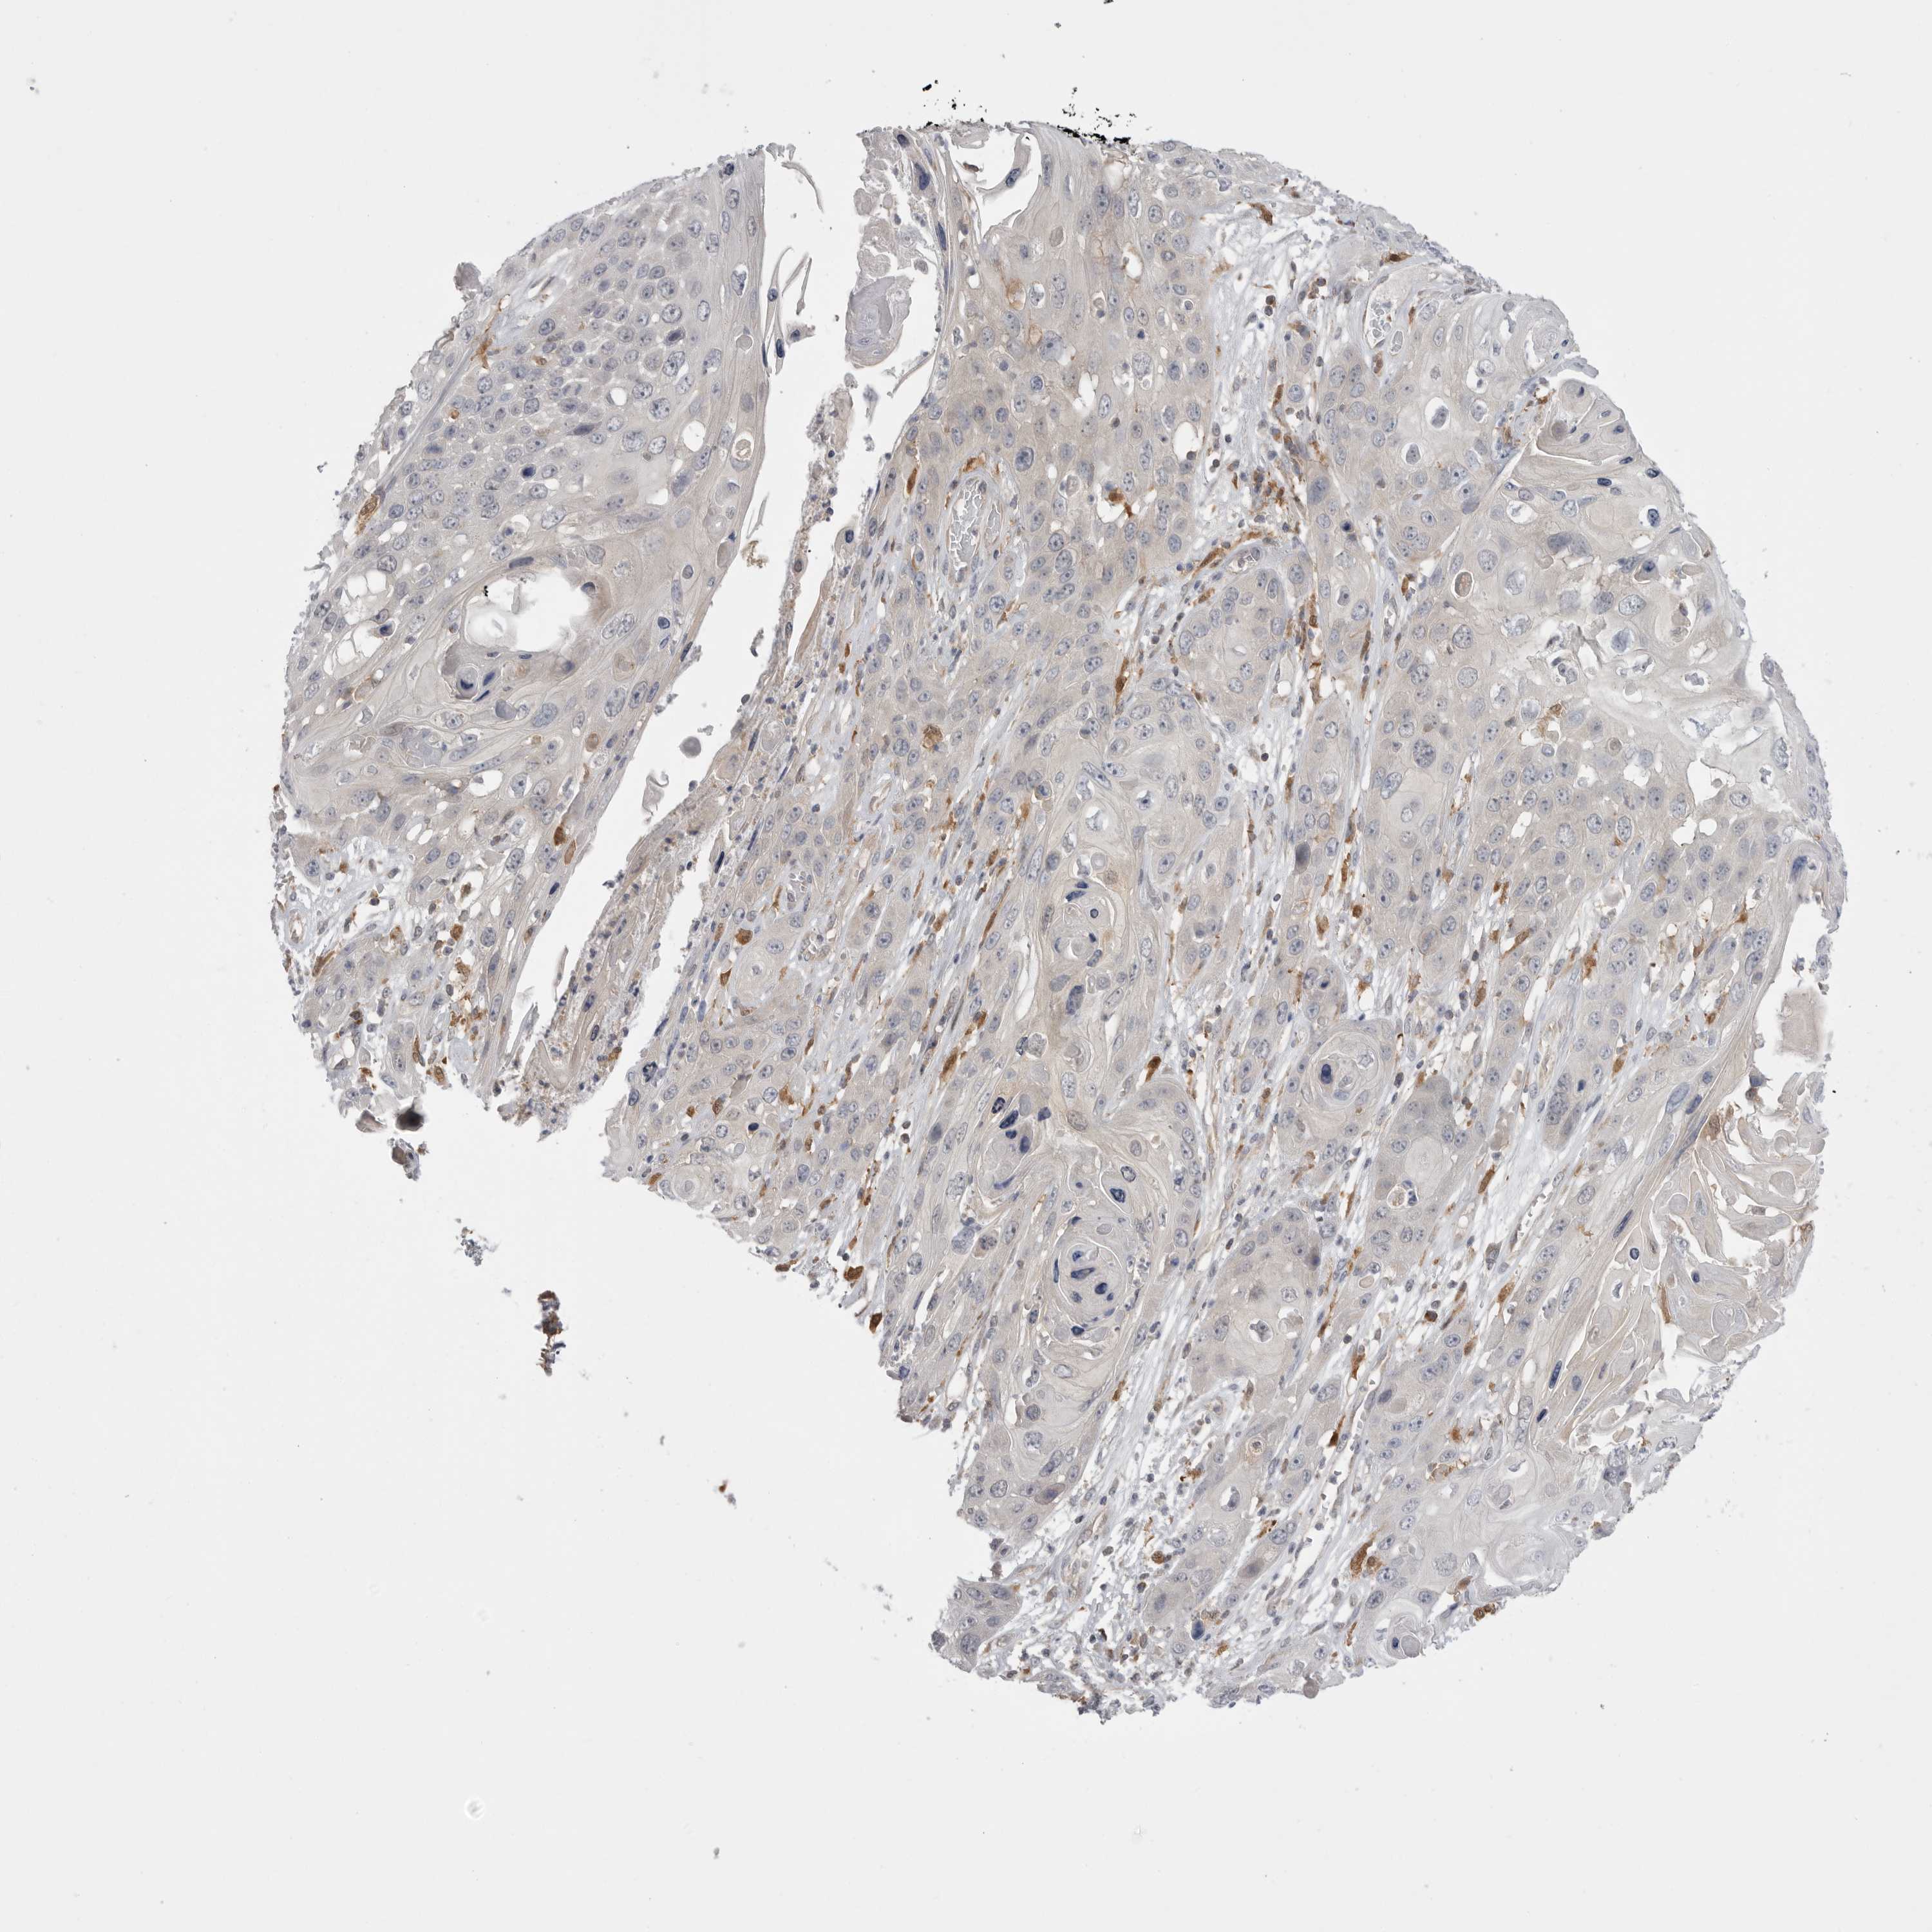

SKIN CANCER - Protein expressioni

A mouse-over function shows sample information and annotation data. Click on an image to view it in a full screen mode. Samples can be filtered based on level of antibody staining by selecting one or several of the following categories: high, medium, low and not detected. The assay and annotation is described here.

Each image is clickable and will lead to virtual microscopy that enables deeper exploration of all samples and also displays staining intensity scores, fraction scores and subcellular localization as well as patient and tissue information for each sample.

Antibody HPA026538

Basal cell carcinoma